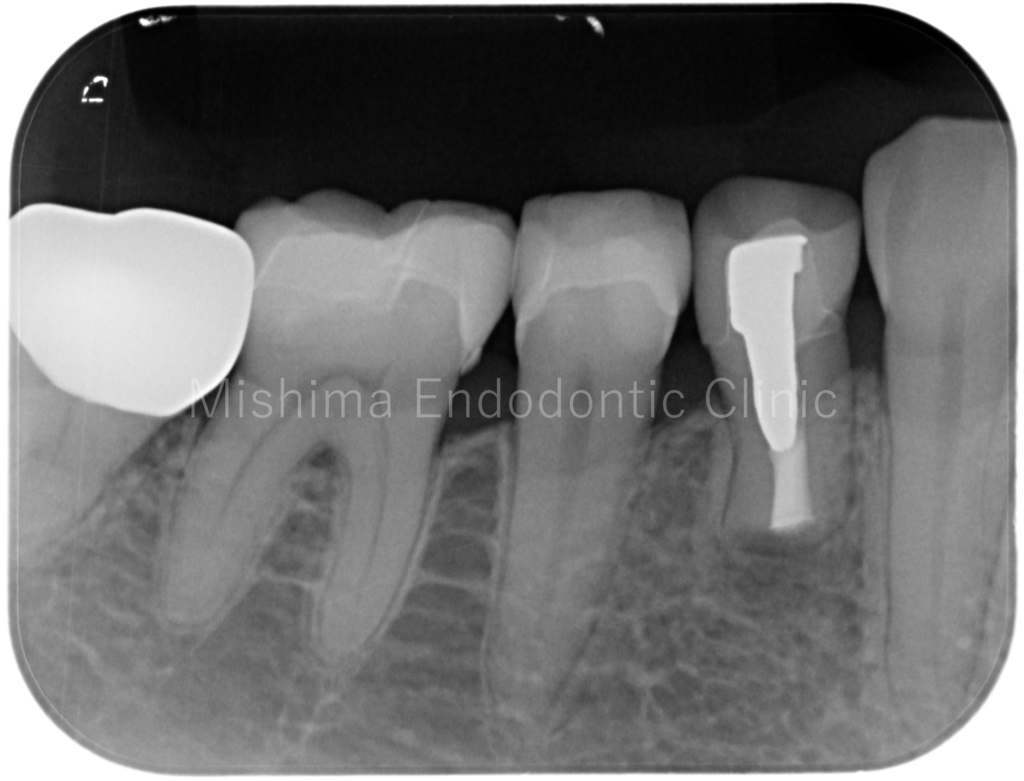

After

| 治療内容 | 他院にて歯根端切除術の既往あり。再歯根端切除術を行い、症状、根尖透過像は消失し、経過は良好。 |

レントゲン